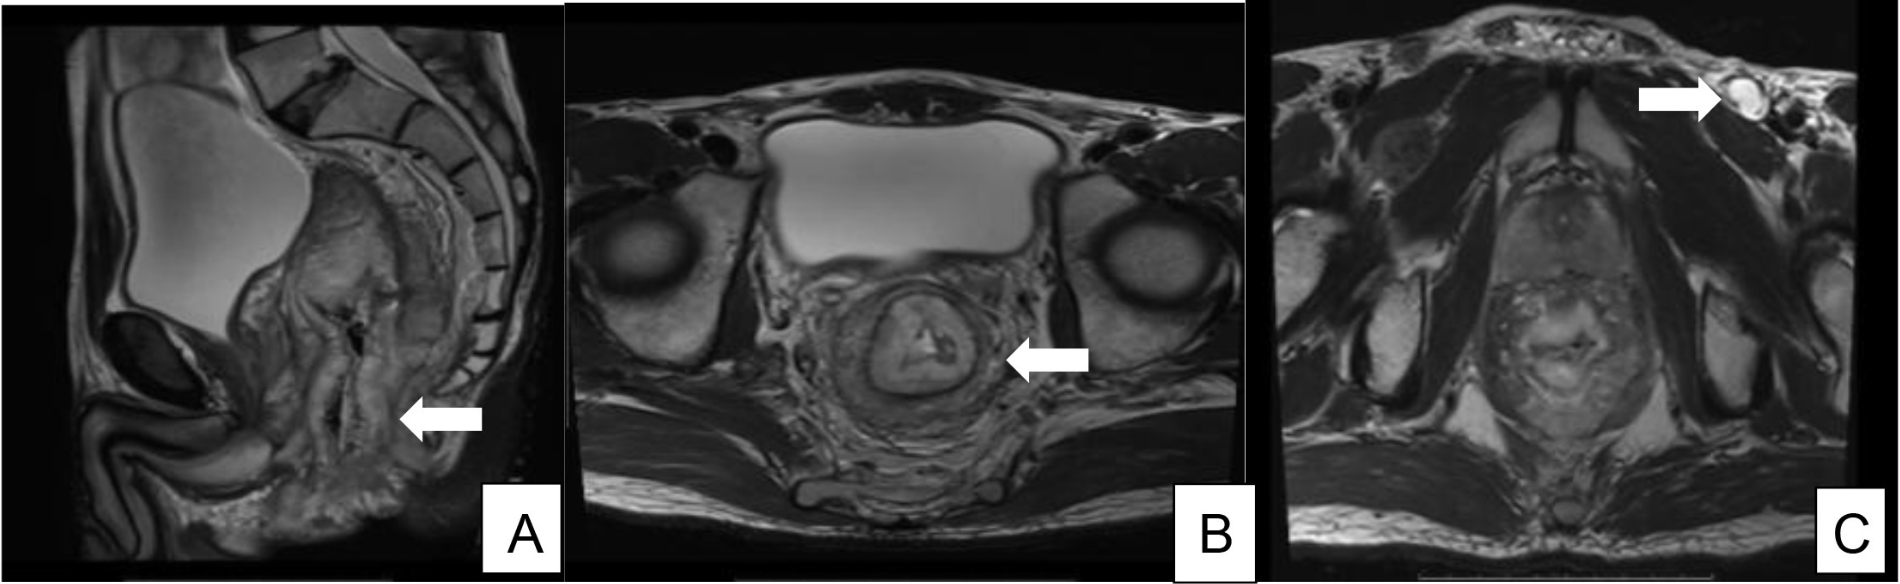

患者接受了预防性结肠造口术以缓解梗阻症状,随后进行新辅助放化疗(卡培他滨联合50.4 Gy放疗)。然而,治疗后MRI显示肿瘤体积增大(图2),且肿瘤已累及提肛肌和整个肛管,无法手术切除。

图2. 放射化疗后评估扫描显示疾病进展,直肠壁肿瘤逐渐增厚,现已延伸至肛门管,以及通过肛门边缘(A 和 B)的膨出外生病变。左腹股沟坏死淋巴结间期发育(C)